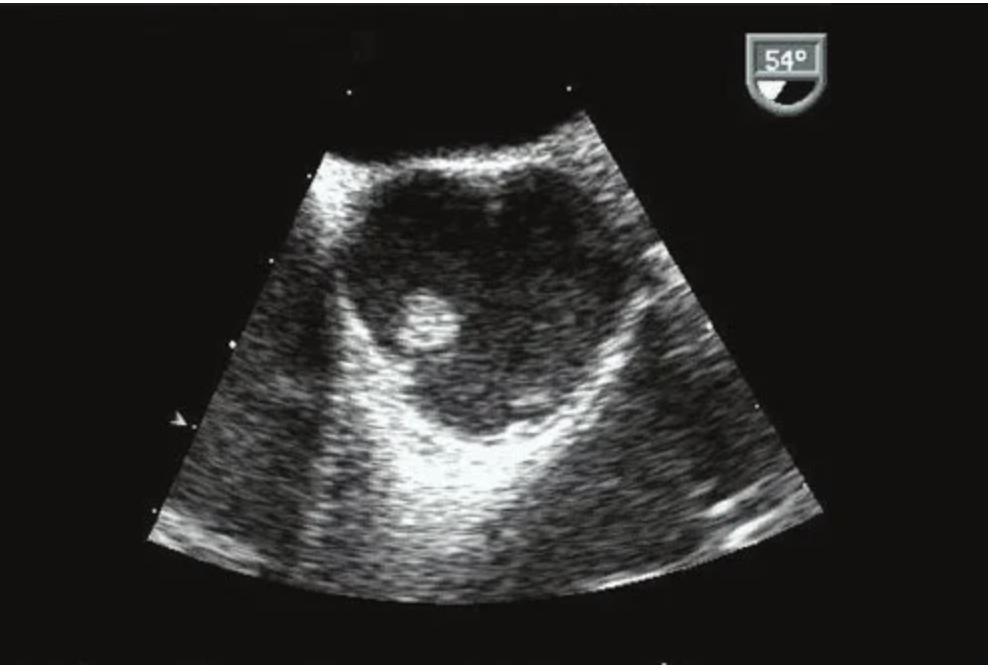

20

Q

This short-axis of the aortic valve in the figure shows?

A

Papillary fibroelastomas are benign tumors that can be seen on the aortic valve. These tumors are described as small, well-delineated, pedunculated masses with a predilection for valvular endocardium. These tumors can be highly mobile and carry an embolic risk. The diagnoses are usually incidental or during investigation for an embolic source. The echocardiographic characteristics of fibroelastomas are:

The tumor is round or oval, irregular in appearance, with well-demarcated borders and a homogeneous texture.

Most are relatively small <20 mm.

Nearly half have small stalks, and those with stalks are mobile.

They may be single or multiple and are often associated with valvular disease.

They more commonly appear on the aortic valve, followed by the mitral valve.